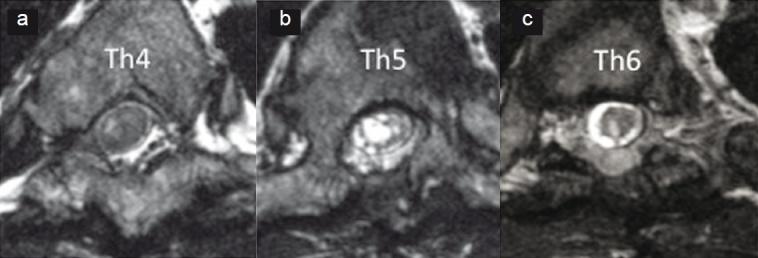

Four consecutive patients with symptomatic syringomyelia or myelomalacia caused by focal adhesive arachnoiditis underwent microsurgical arachnoidolysis. Comprehensive imaging evaluation using constructive interference in steady-state (CISS) magnetic resonance imaging (MRI) or myelographic MR imaging using true fast imaging with steady-state precession (TrueFISP) sequences was included before surgery to determine the surgical indication.

4例因局灶性粘连性蛛网膜炎导致有症状的脊髓空洞症或脊髓软化的患者接受了显微外科蛛网膜松解术。术前采用稳态构成干扰(CISS)磁共振成像(MRI)或使用稳态进动快速成像(TrueFISP)序列的脊髓造影MRI进行全面的影像学评估,以确定手术指征。